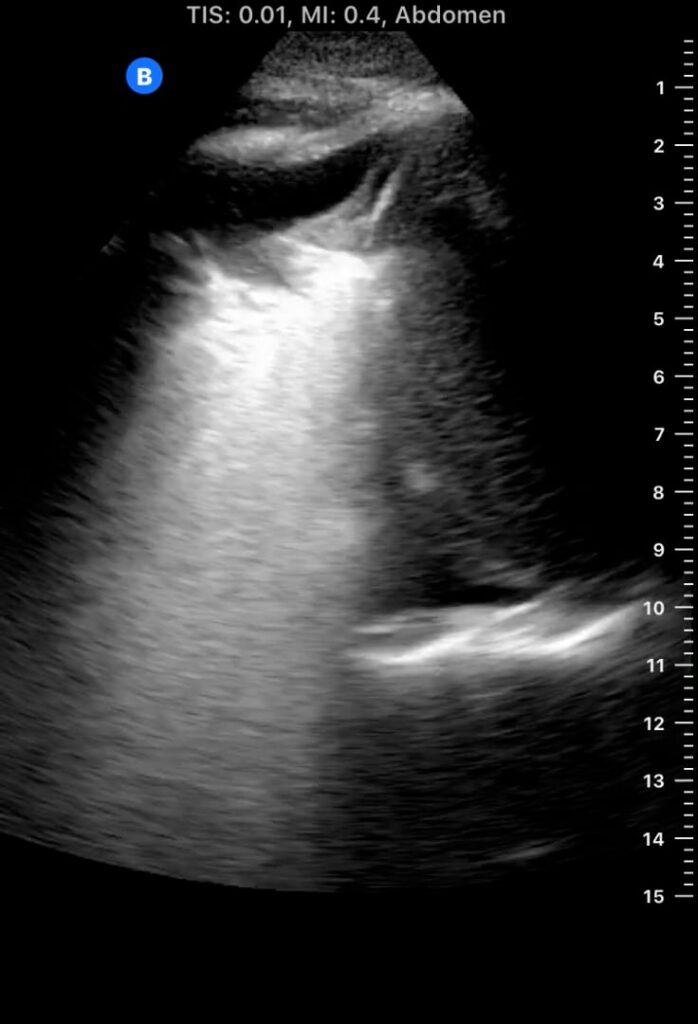

Lung consolidation in medical ultrasound refers to the solidification of lung tissue due to the accumulation of fluid, cells, or other substances, replacing the air within the alveoli. This pathological change commonly indicates conditions like pneumonia or atelectasis. On ultrasound, consolidated lung appears hyperechoic (bright) with a tissue-like echotexture, often resembling the liver (hepatization).

Identifying lung consolidation via ultrasound is crucial for rapid diagnosis and management in acute care settings. This non-invasive imaging technique allows clinicians to visualize air bronchograms (air-filled bronchi within consolidated tissue) and pleural effusions, aiding in differentiation from other lung pathologies. Ultrasound offers a portable and radiation-free alternative for bedside assessment of lung parenchyma, optimizing patient care.